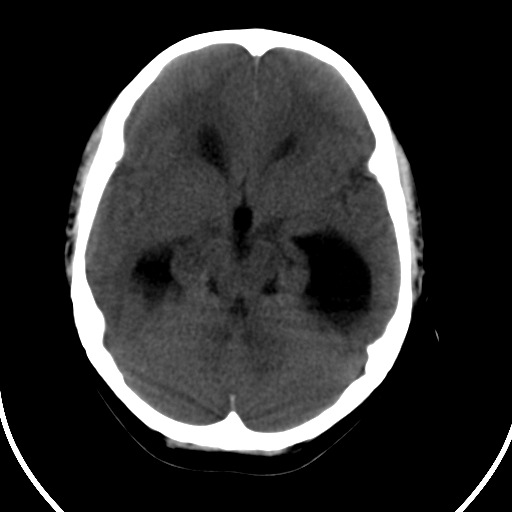

男,11岁

重度脑积水,但第四脑室扩大不明显,考虑导水管阻塞,建议mr。

右额叶内见一边界清楚,脑脊液密度的囊腔,无灰质内衬,并与脑室相通,四室以上脑室系统高度扩张。诊断:先天性脑穿通畸形伴梗阻性脑积水

脑穿通畸形并梗阻性脑积水.